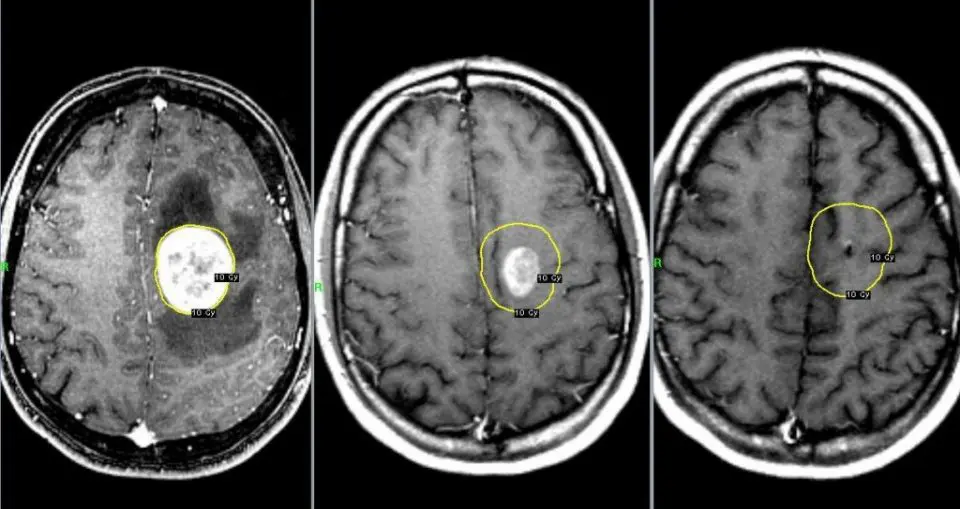

Діагностика – МРТ з контрастом, біопсія. Без неї важко відрізнити від інсульту чи деменції. Раннє виявлення рідкість; більшість приходить, коли пухлина вже панує.

З моменту виявлення до кінця минає 12-18 місяців за лікуванням – стандарт хірургії, радіації й хіміотерапії темозоломідом. Без неї – 3-6 місяців. Перші місяці: операція видаляє 90% пухлини (якщо можливо), стероїди зменшують набряк. Пацієнт повертається до рутини, але рецидив неминучий – у 95% протягом року.